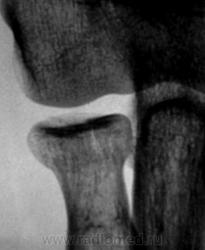

Фрагменты с увеличением.

Хочется услышать мнение коллег по поводу "жировых подушечек". Как они, среагировали или нет?

Следовательно, "отклонение" жировой ткани в виде образования "жировых подушечек", не свидетельствует, как утверждают многие, прямо, именно, о переломе, а свидетельствуют только о гемартрозе?